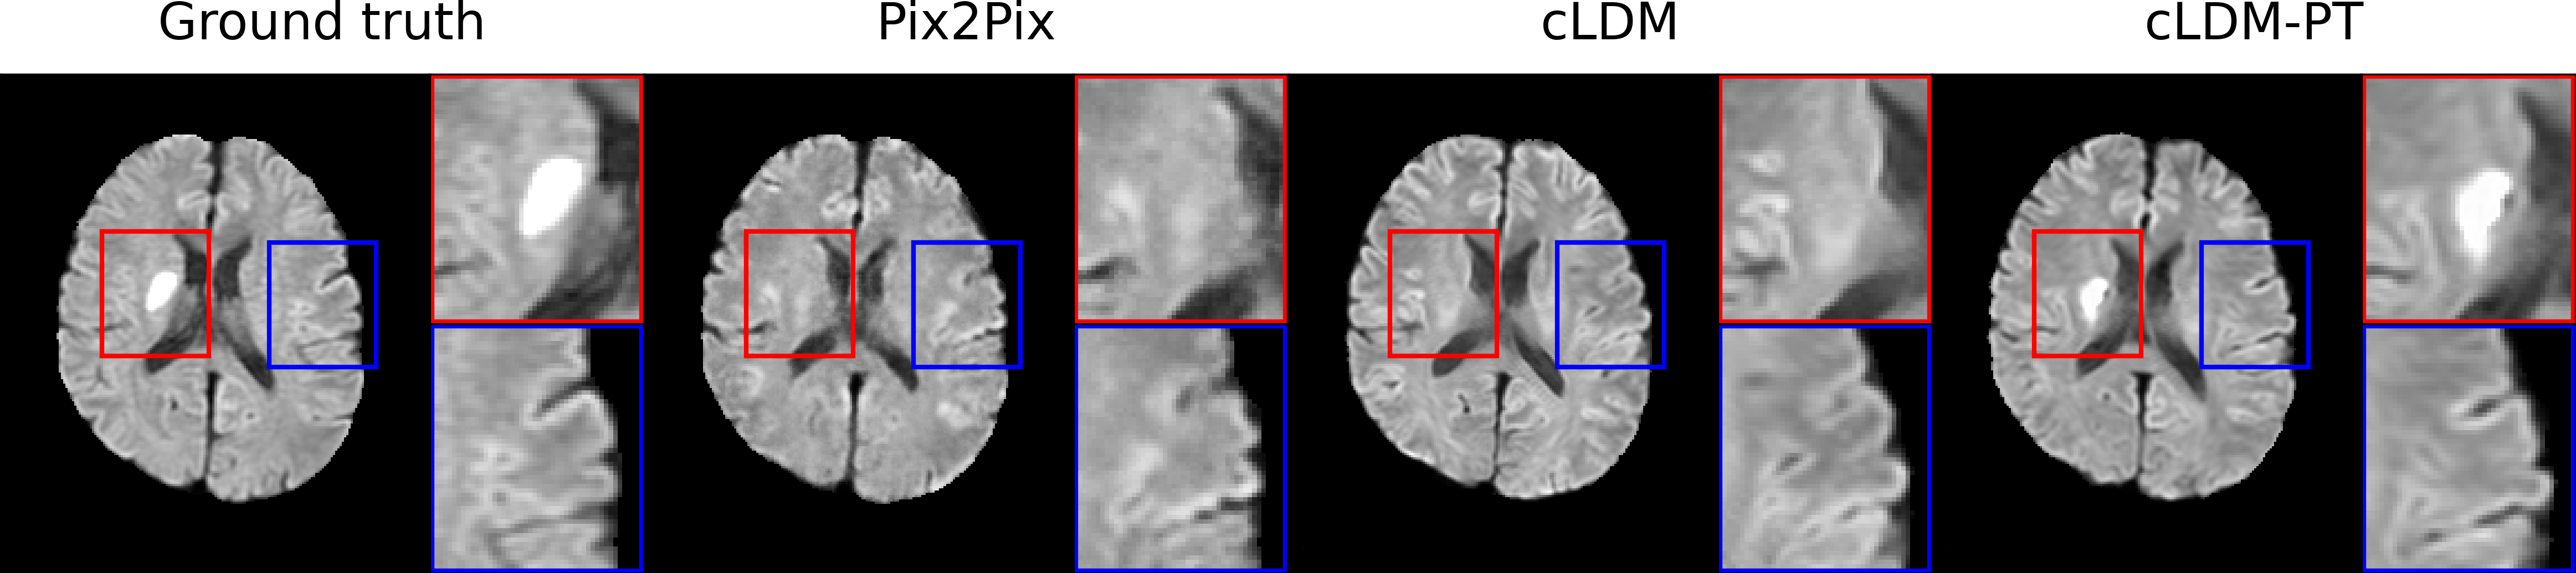

3.2.2 Qualitative Evaluation

Figure 3 visualizes synthesized DWI and ADC from CTP of acute ischemic stroke patients with lesions in various brain regions. Due to low signal-to-noise ratio of CTP, it is difficult to accurately estimate ischemic core volumes. Small infarcts such as lacunar infarcts are also poorly visualized in CTP. These factors make it challenging for generative models to accurately reconstruct ischemic lesions in synthesized MRI. While the diffusion model series generates more realistic images compared to GAN-based models, they encounter difficulty in lesion delineation. Our model, cLDM-PT, excels in lesion delineation and demonstrates exceptional ability to generate accurate and detailed images.